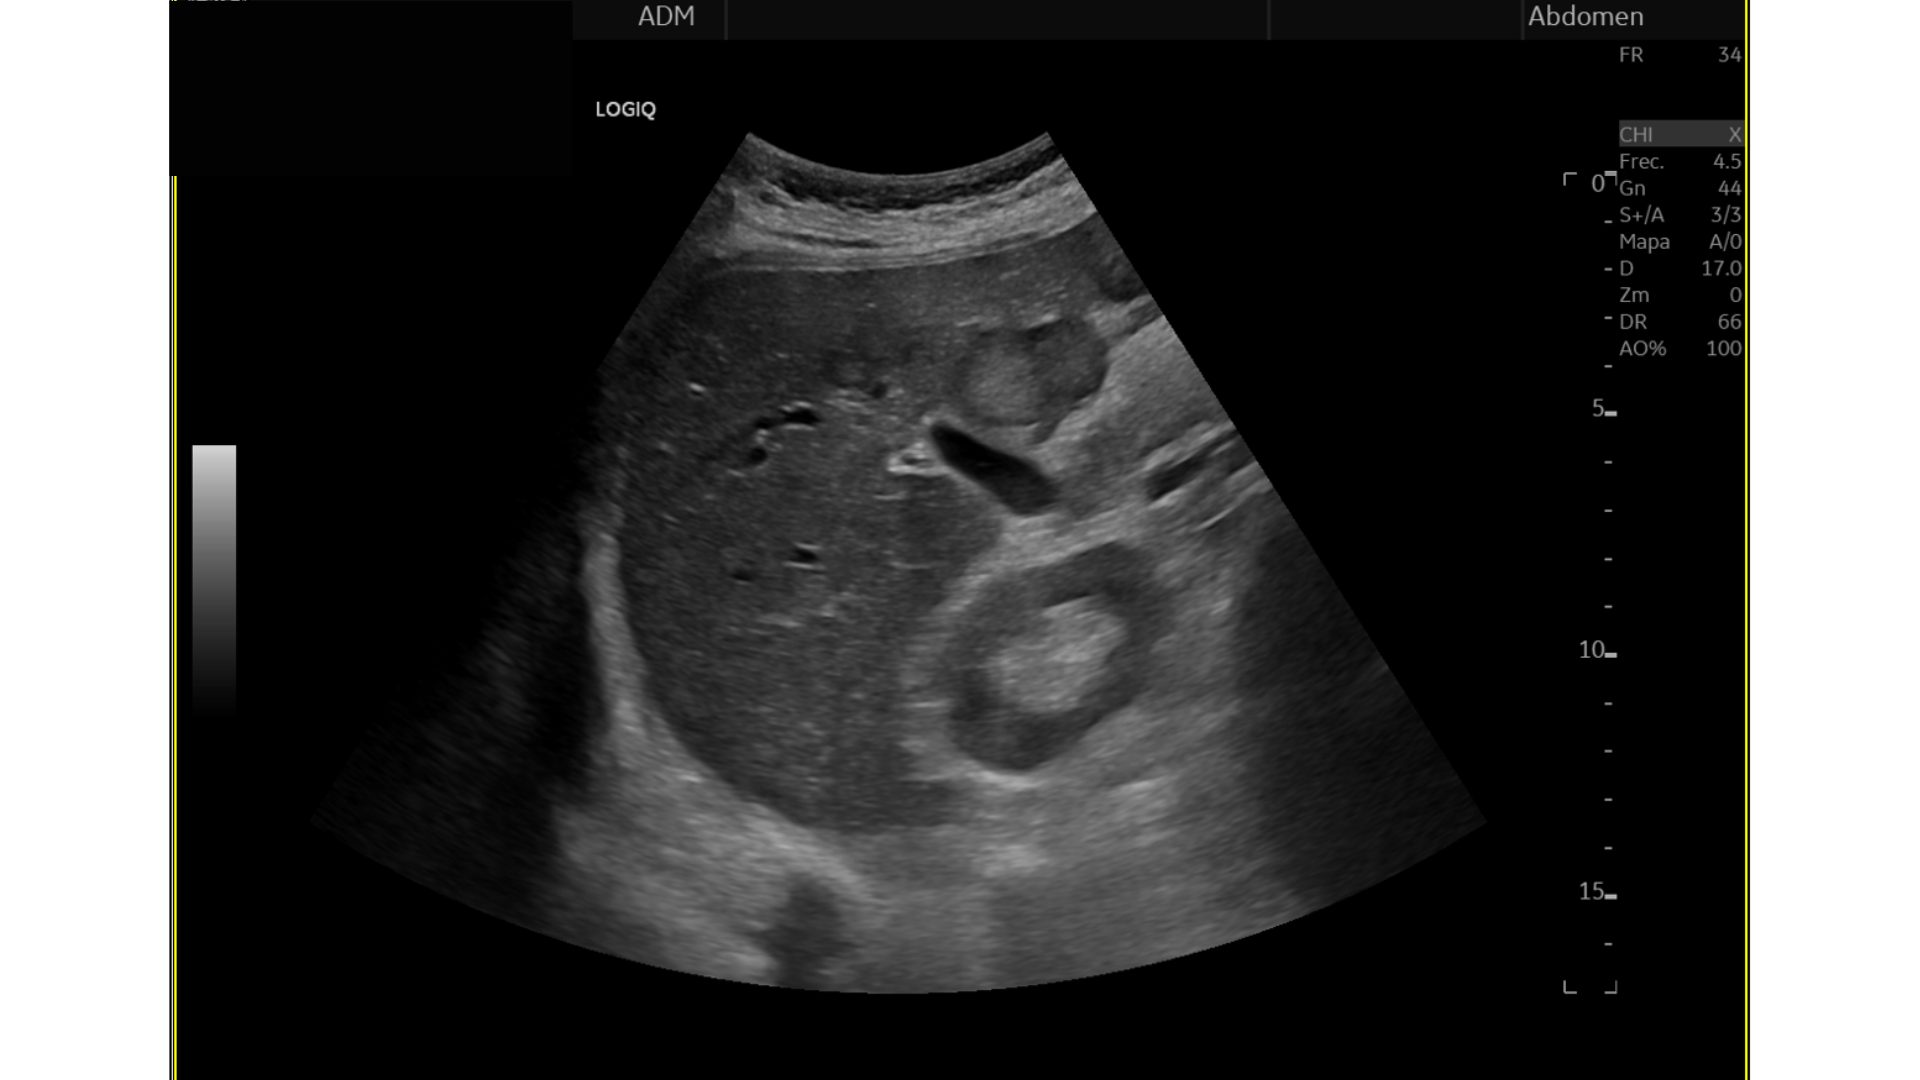

Eco Abdominal: Múltiples imágenes nodulares heterogéneas en ambos lóbulos hepáticos sugestivas de M1. Destaca imágen nodular, hipoecogénica en cabeza/cuerpo de páncreas de aprox. 17 mm, podría corresponderse con proceso neoformativo primario.